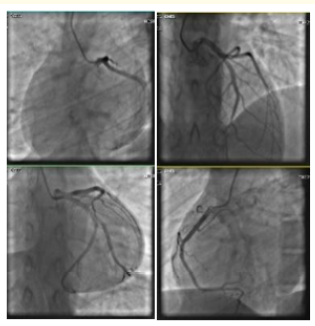

Case Report

Acute Myocardial Infarction in Adolescents. Case Report

Ramírez Ortega M, Pérez Ochoa E, León López M, Aguilar Cózatl I, Soancatl Rodríguez LG, Soancatl Rodríguez DG, Porras Aguilar E and Martínez Tovilla Y. 12(9): 01-13.